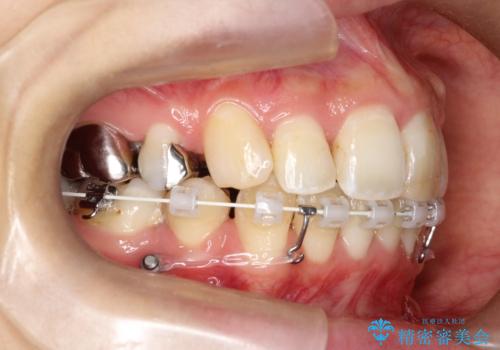

- 口元が出ていることを気にされて来院されました。精密な検査の結果、歯列全体のスペースが不足していることが判明。患者様のご希望である「口元を下げたい」というご要望を叶えるため、上下左右の小臼歯を抜歯し、そのスペースを利用して前歯を奥へ移動させる治療計画を立案しました。また、仕事上、目立つ矯正装置を避けたいというご希望から、上顎に裏側矯正、下顎に表側矯正を組み合わせたハーフリンガル矯正を提案しました。

今回の矯正治療では、口元を大きく下げるため、上下左右の小臼歯を抜歯しました。装置には、上顎は歯の裏側に装着する裏側矯正(舌側矯正)を、下顎は透明で目立ちにくい審美ブラケットを使用するハーフリンガル矯正を選択。これにより、治療中も他人の目を気にすることなく、ストレスなく過ごしていただけました。抜歯によってできたスペースを有効活用し、歯列全体を後方へ移動させることで、口元の突出感を解消。治療の結果、口元がすっきりと整い、自信のある美しい横顔を獲得していただけました。